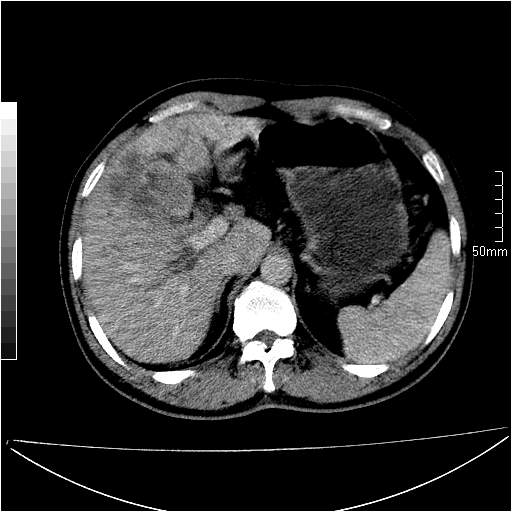

男性,54岁,皮肤黄染,搔痒一周余.b超示肝左叶回声异常.初步诊断1胆总管下段结石2胆囊结石伴慢性胆囊炎请各位战友帮忙看一下肝脏多发低密度如何解释恰当.增强效果不是很好.请大家见谅.

既然做了增强,为什么光提供延时期片子,肝动静脉期肝右叶前下段病灶增强如何?另外胆囊壁增厚,欠规整,内密度不均,与肝右叶病灶分界不清,增强表现怎样?肝内胆管轻度扩张,胆总管扩张,但未见明显结石影,也应提供增强早期图像才好鉴别扩张原因。片子较清,但不够完整,暂考虑1.胆囊癌肝局部浸润,或肝癌胆囊侵犯,2.胆总管下端或胰头钩突部占位。总之本人看不明白,请高手画图指示,先谢了!

由于胆囊窝内结构显示不清,肝脏病灶又邻近胆囊窝首先考虑胆囊癌肝受侵犯。而后因肝脏病灶强化有渐进改变,且相邻胆管扩张,故考虑肝胆管细胞癌待排。

左肝胆管细胞癌。

胆总管下端结石。